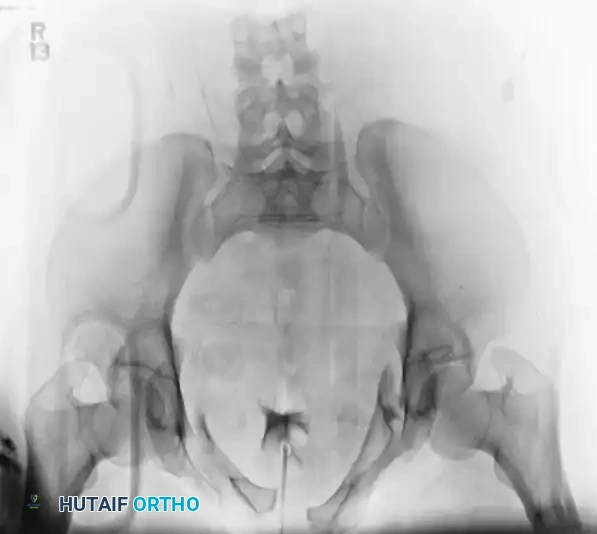

An AP III injury is a completely unstable pelvic ring disruption. It involves complete disruption of the symphysis pubis (or anterior rami) and complete disruption of both the anterior and posterior sacroiliac ligamentous complexes. The hemipelvis is both rotationally and vertically unstable.

The preoperative AP, inlet, and outlet views demonstrate severe pubic diastasis, bilateral pubic rami fractures, and gross widening/displacement of the posterior SI joints.

FIGURE 56-45: Young and Burgess anteroposterior type III (AP III) pelvic ring injury with pubic diastasis and bilateral pubic rami fractures. A-C, Preoperative anteroposterior, inlet, and outlet views, respectively. D, Preoperative CT scan.